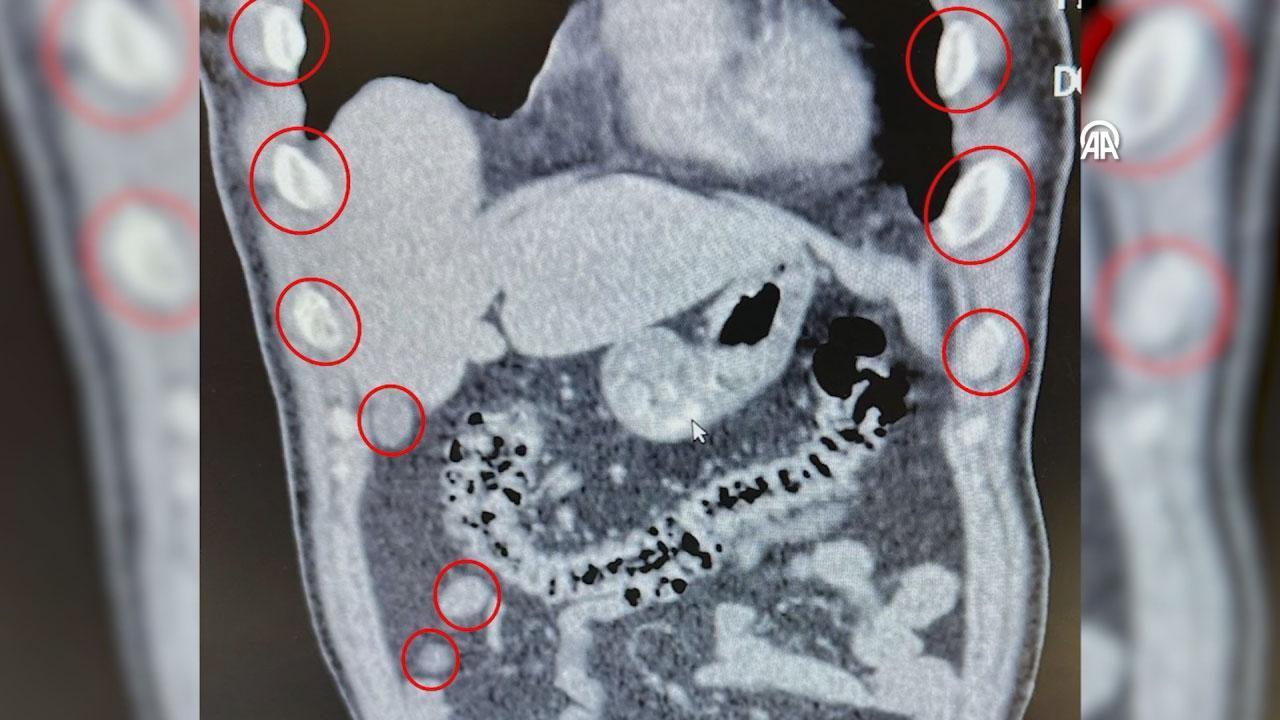

Bitlis Tatvan Devlet Hastanesine götürülen şüphelilerin röntgen ve tomografilerinde, mide ve bağırsaklarında çok sayıda yabancı cisim olduğu belirlendi.

Şüphelilerin yuttuğu 136 kapsüldeki 1 kilo 48 gram sentetik uyuşturucu, tıbbi müdahaleyle mide ve bağırsaklardan çıkarıldı.